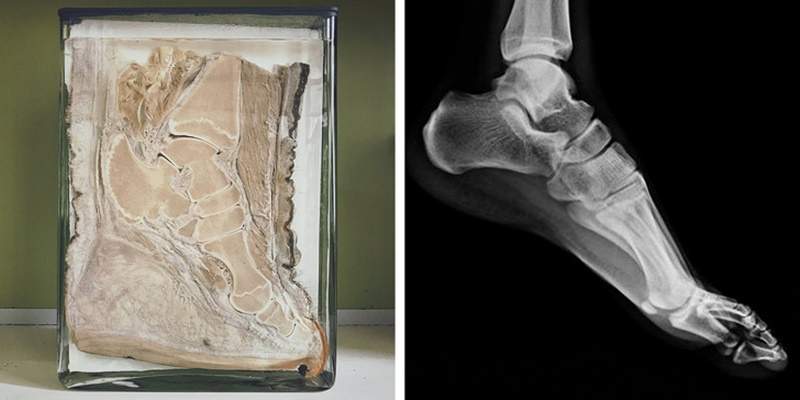

▼大象:牠們腳部的骨骼跟人類的骨骼結構很相似。